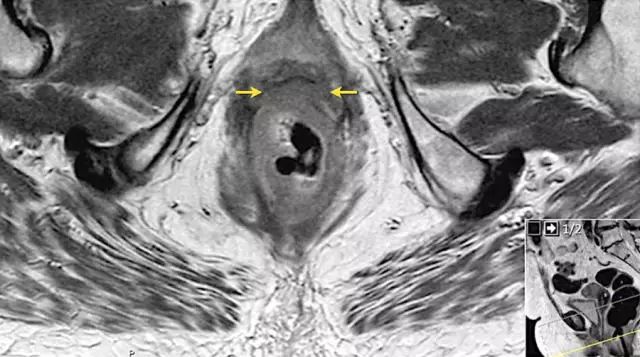

T4b 分期,侵入周围器官

T4 期肿瘤侵犯周围结构,如盆壁、阴道、前列腺、膀胱或精囊,这类局部晚期患者需要进行长程放化疗和广泛切除。

图 16 在矢状 T2W 图像上,直肠和阴道后壁之间有脂肪平面的损失。在轴向图像上,看到肿瘤的相对低的信号强度延伸到阴道的后壁(箭头)

以下 5 幅图例请连续观看:

图 17~21 肿瘤的低信号强度延伸到阴道的后壁(箭头)

图 22 浸润到子宫后壁的肿瘤